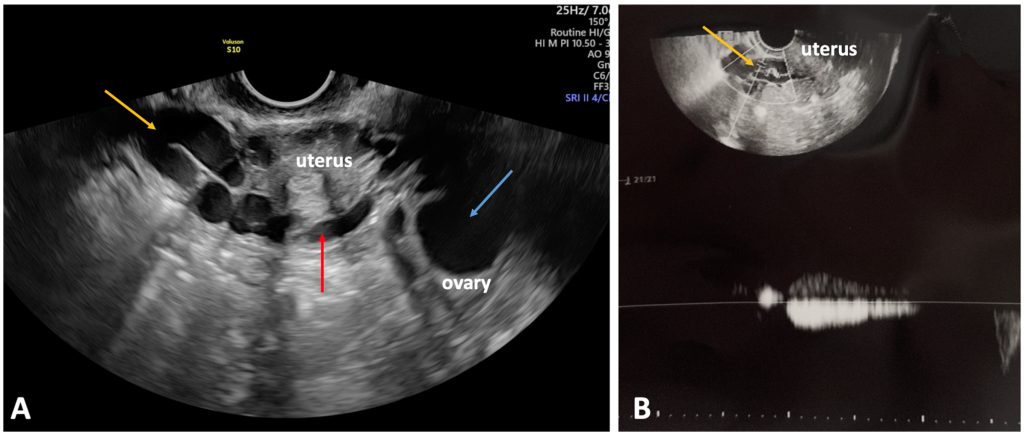

Оно играет важнейшую роль в исключении альтернативных причин хронической тазовой боли, особенно гинекологических заболеваний, таких как эндометриоз, аденомиоз, кисты яичников и миомы. Наличие расширенных тазовых венозных сплетений и вены шириной более 5 мм, пересекающей тело матки и соединяющей расширенные периматочные венозные сплетения с обеих сторон матки (рис.3), считается высокочувствительным и специфичным признаком заболеваний вен малого таза.[3].

Рисунок 3. (А) Варикозно расширенные вены периматочного венозного сплетения (желтая стрелка), расположенные рядом с маткой и соединенные с веной, проходящей через тело матки (красная стрелка). (B) Рефлюкс (продолжительность: 2 с) в околоматочном венозном сплетении (желтая стрелка) после дистального ручного компрессионного воздействия в ипсилатеральной подвздошной ямке.